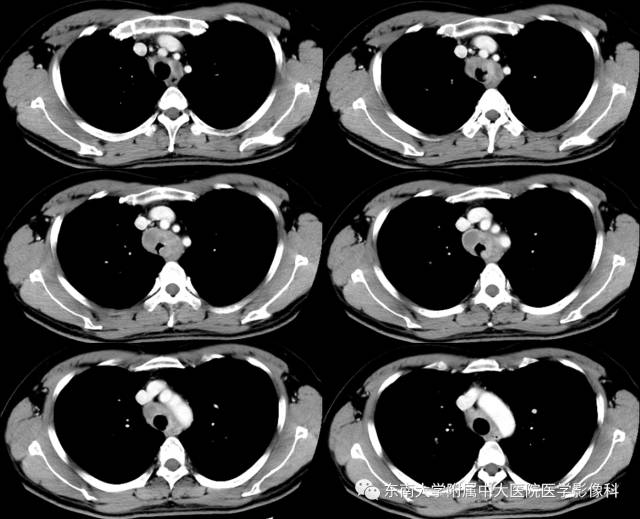

病例1

CT

平扫 增强